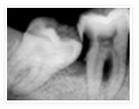

阻生牙是指由于种种原因,致使牙齿部分萌出或完全不能萌出,并且以后也不能萌出的牙。

就是我们说的智慧牙,医学名词叫阻生牙,即:牙齿在颌骨内由于位置不正,不能萌出到正常咬合位置,这样的牙称为阻生牙。由于阻生牙的牙冠部分或全部为牙龈覆盖,在牙龈与牙冠之间就形成细菌繁殖区,当机体抵抗力下降或细菌毒力增强时就会引起冠周发炎。冠周发炎意味着牙疼不是病,疼起来要人命..

人们常说的"尽头牙"在口腔医学中称"智齿",也叫第三磨牙。它是人类口腔中萌出最晚的一颗牙,往往在18-25岁才萌出。随着人类的进化,由于颌骨变小,而没有足够的位置,从而形成智齿错位萌出,这种牙又叫阻生牙。它往往会使牙冠周围软组织产生炎症,即"尽头牙"发炎。这种牙不但无功能反而有害,必须尽早拔除,以防止进一步发炎。